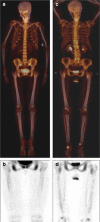

Results: They focused on coronary (n = 8), carotid (n = 7), and femoral arteries (n = 1), thoracic aorta (n = 1), and infrarenal aorta (n = 1). The remaining 15 studies examined more than one arterial segment. The literature was heterogeneous: few studies were designed to investigate atherosclerosis, 13 were retrospective, 9 applied both FDG and NaF as tracers, 24 NaF only. Subjective quality was low in one, medium in 13, and high in 19 studies. The literature indicates that NaF is a very specific tracer that mimics active arterial wall microcalcification, which is positively associated with cardiovascular risk. Arterial NaF uptake often presents before CT-calcification, tends to decrease with increasing density of CT-calcification, and appears, rather than FDG-avid foci, to progress to CT-calcification. It is mainly surface localized, increases with age with a wide scatter but without an obvious sex difference. NaF-avid microcalcification can occur in fatty streaks, but the degree of progression to CT-calcification is unknown. It remains unknown whether medical therapy influences microcalcification. The literature held no therapeutic or randomized controlled trials.

Conclusion: The literature was heterogeneous and with few clear cut messages. NaF-PET is a new approach to detect and quantify microcalcification in early-stage atherosclerosis. NaF uptake correlates with cardiovascular risk factors and appears to be a good measure of the body's atherosclerotic burden, potentially suited also for assessment of anti-atherosclerotic therapy.